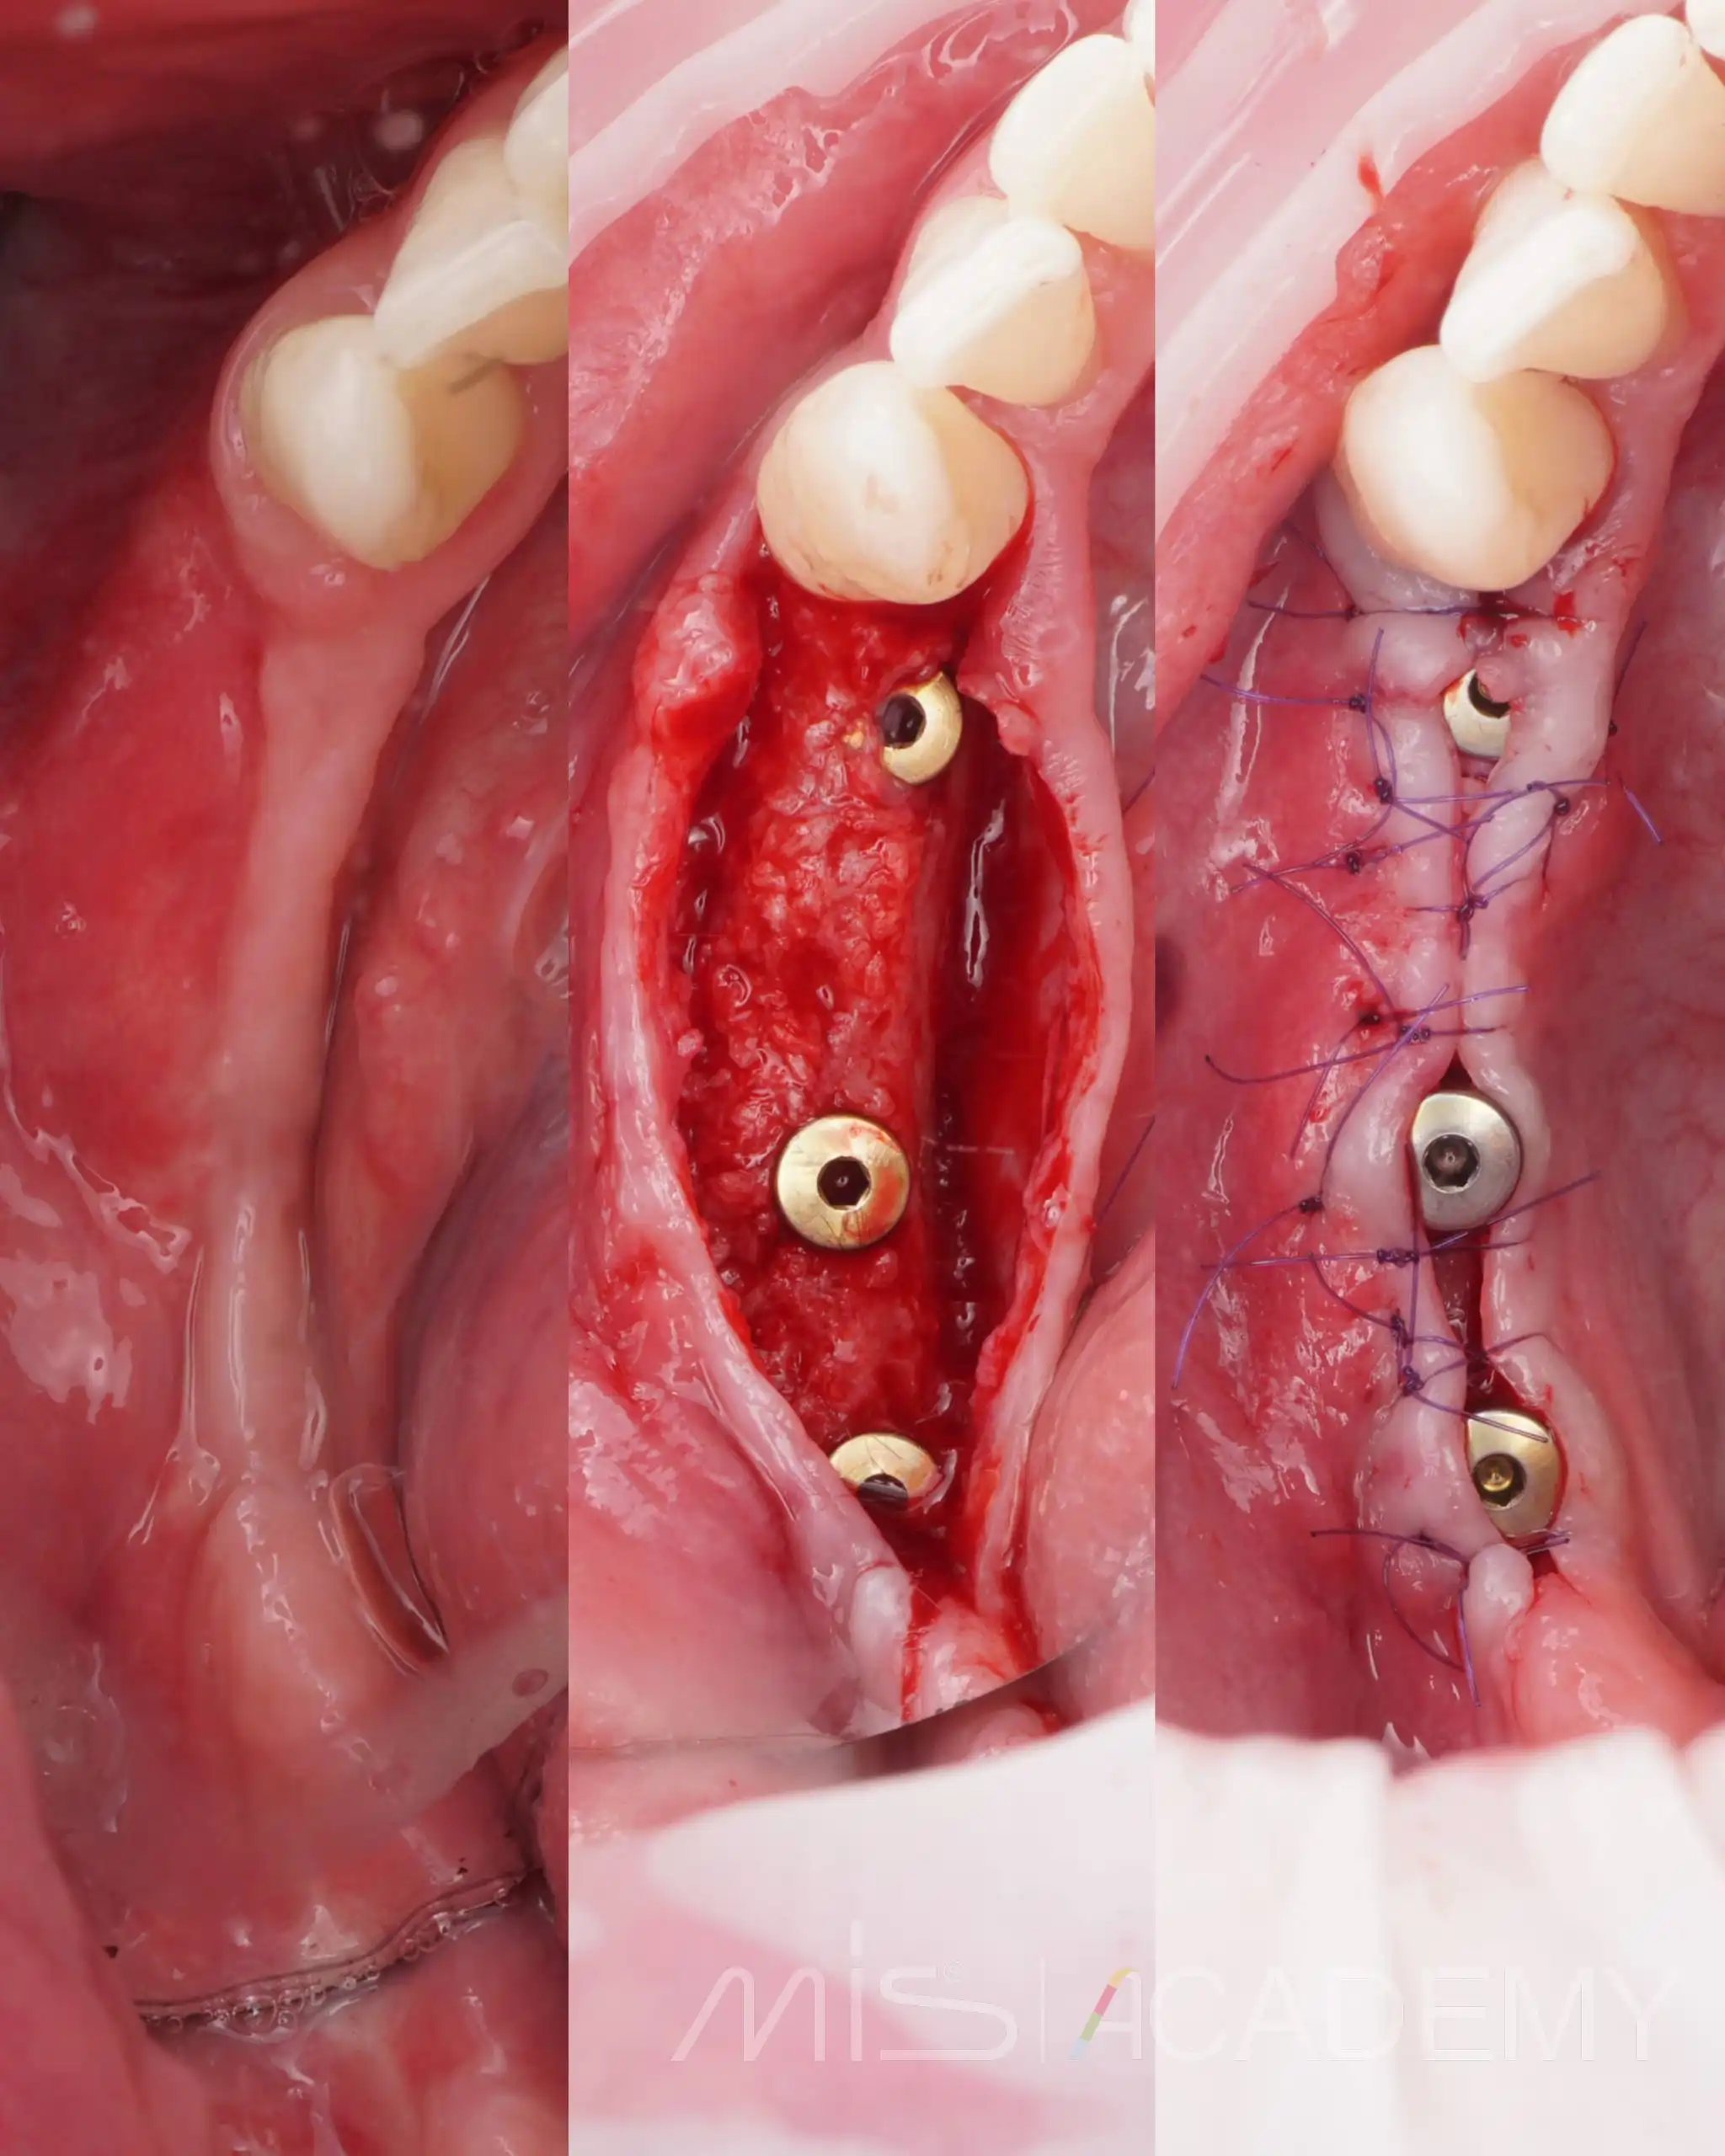

Второй этап нижняя челюсть:

В боковых отделах выраженная атрофия по ширине и высоте. При планировании приняли решение об имплантации с одновременной костной аугментацией по ширине.

— Установлены имплантаты MIS C1.

— Connect абатменты с заглушками, которые дополнительно сработали как тенты.

— Костная пластика материалами Osteobiol: справа ксено MP3 с Derma, слева Gen-Os с нативным коллагеном и Lamina Curved, ушивание.

Через 6 месяцев выполнено раскрытие, замена заглушек на формирователи десны на коннектах и пластика мягких тканей.